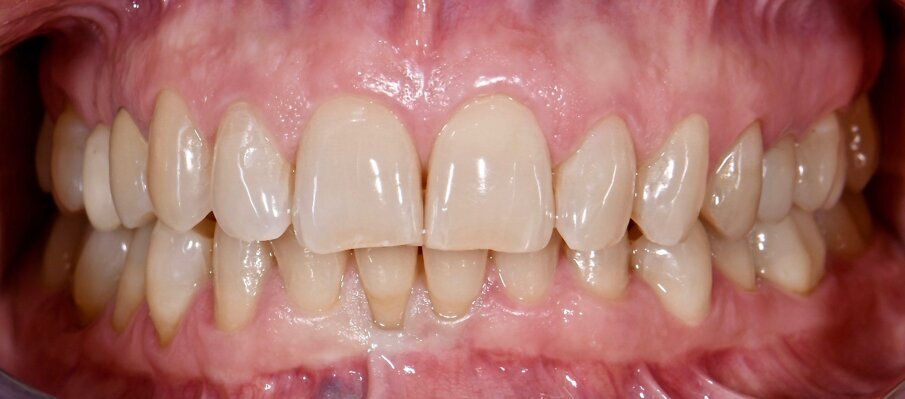

Materiali e metodi Case report Il presente case report è stato redatto in accordo con il CARE checklist (https://www.carestatement.org/checklist, consultato il 29 Gennaio 2024). Una paziente italiana di 44 anni, non fumatrice si è recata alla S.C Riabilitazione Orale Protesi Maxillo-Facciale e Implantologia Dentaria della Dental School dell’Università degli Studi di Torino nel mese di Gennaio 2023, lamentando sanguinamento gengivale durante lo spazzolamento. La paziente ha firmato un consenso informato. L’anamnesi medica della paziente non era rilevante. All’esame intraorale si evidenziava una scarsa igiene orale e la presenza di impianti in sito 15 e 25 (Figg. 1a-1c). I parametri parodontali al baseline sono stati riportati in Figura 2.

Fig. 1a - Condizione clinica al baseline: visione frontale.

Il Full Mouth Plaque Score (FMPS) era 71%, il Full Mouth Bleeding Score (FMBS) era 24% ed è stata osservata una profondità di sondaggio ≥ 4 mm nel 9,5% dei siti, localizzata a livello dei molari e premolari di entrambe le arcate. L’impianto in situ 15 (Nobel Replace, diametro 4,3mm, lunghezza 13mm) e l’impianto in situ 25 (Sweden & Martina SYRA, diametro 4,25 mm, lunghezza 1 mm) presentavano placca e una mucosa peri-implantare eritematosa ed edematosa. Per ciò che concerne l’impianto 15, si era riscontrata una moderata (PPD 4-5 mm) e severa (PPD≥ 6 mm) profondità di sondaggio, con una profondità media di 3.33 mm. FMBS e FMPS erano del 100%, così come riportato in Figura 2. La rilevazione dei parametri peri-implantari dell’impianto 25 aveva evidenziato PPD moderati nel 67% dei siti e una PPD severa a livello mesio-vestibolare. FMPS e FMBS erano 100%.